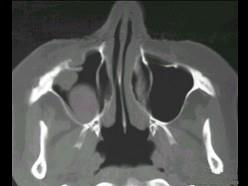

问题 女性,50岁,右鼻塞、脓涕3个月,CT、MRI检查如图所示,请选择正确的答案 ( )

选项 A、右侧上颌窦黏液腺瘤 B、右侧上颌窦腺样囊性癌 C、右侧上颌窦粘膜下囊肿 D、右侧上颌窦积液 E、右侧上颌窦黏液囊肿

答案 B